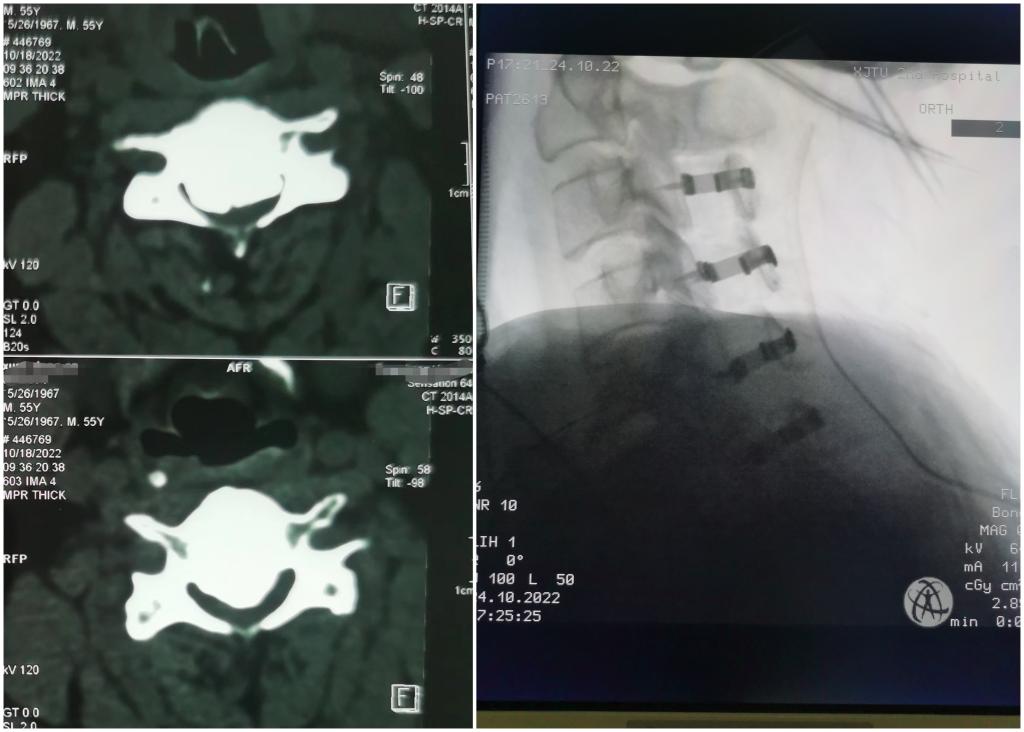

骨三科完成高难颈椎OPLL手术,濒临瘫痪患者重获新生

近日,一名来自我市新城区极重度颈椎后纵韧带骨化(OPLL)脊髓损伤患者在我院骨三科成功接受高难度手术,脊髓神经压迫解除,症状缓解,平稳度过围手术期。 患者华XX(化名),突发颈部以下感觉麻木,不能正常行走,双手不能活动。...